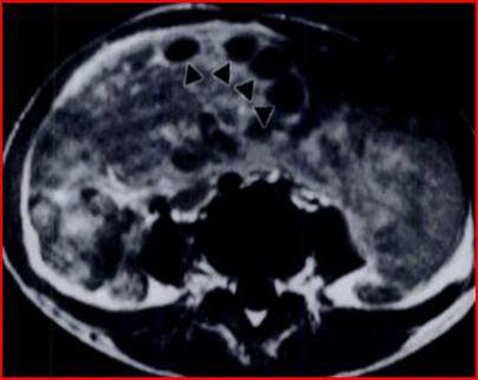

Figures 7 and 8: Axial CT images with contrast medium 7-8 show two masses (arrow points), one in the pelvis (Figure 7) and one in the left iliac fossa (Figure 8). The masses tend to displace the surrounding organs and free fluid is observed in the right area. Small retroperitoneal lymph nodes are also noted in the left paraaortic region (black arrow).

Abdominal and pelvic CT shows two contiguous solid masses. The small cysts on the periphery of the masses, identified by ultrasound and MRI, are not shown by CT which instead highlights the presence of some small retroperitoneal lymph nodes of approximately 1 cm. (Figures 7 and 8). There was no further adenopathy and the spleen was normal. Furthermore, the bone marrow aspirate did not contain infiltrates.

The analyzed tissue shows the presence of a diffuse infiltration of intermediate-sized lymphoid cells with scant cytoplasm and round nuclei with areas of pleomorphism. The nuclei contain multiple nucleoli and frequent miosis is present. (Figure 9) The cells express CD20, CD10, bcl-6, and IgM but are negative for bcl-2. The nuclei Cytology demonstrates the presence of traslocation t (8; 14), given that it supports the diagnosis of Burkitt’s lymphoma with ovarian localization. The patient began chemotherapy treatment and CT performed 6 weeks after therapy showed a dramatic reduction in the volume of the mass. (Figure 10).

Figure 9: Hematoxylin-eosin section shows a diffuse population of medium-sized cells, with some dispersed macrophages. There are frequent mitoses and abundant apoptosis.

Figure 10: CT with contrast medium, performed six weeks after administration of two cycles of chemotherapy. The tumor (arrowheads) has significantly reduced in size.